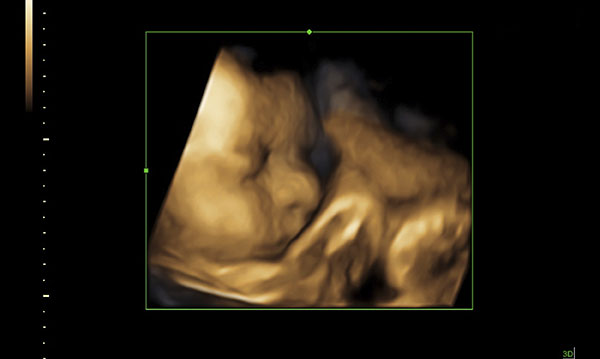

Advances in technology allow parents preparing for baby’s arrival to get a glimpse at what their little boy or girl will look like weeks before their bundle of joy is even born. Long past the days of difficult-to-decipher ultrasound pictures, as 3D-4D ultrasound options let parents see a baby’s unique features.

Parents-to-be can even count baby’s fingers and toes on the ultrasound screen – maybe even making out mom or dad’s nose or the same chubby cheeks a sibling has.